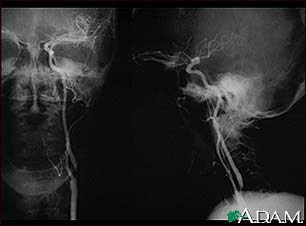

Carotid stenosis - X-ray of the left artery

Carotid stenosis - X-ray of the right artery

- Angiogram of the head to look for a blood vessel that is blocked or bleeding